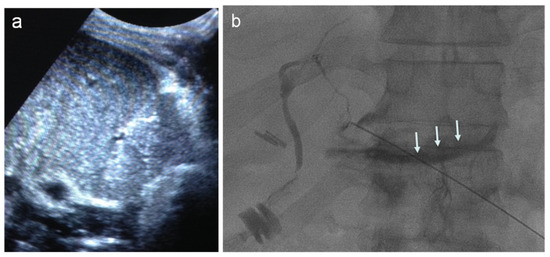

- Venturini, M.; Sallemi, C.; Marra, P.; Palmisano, A.; Agostini, G.; Lanza, C.; Balzano, G.; Falconi, M.; Secchi, A.; Fiorina, P.; et al. Allo- and auto-percutaneous intra-portal pancreatic islet transplantation (PIPIT) for diabetes cure and prevention: The role of imaging and interventional radiology. Gland. Surg. 2018, 7, 117–131. [Google Scholar] [CrossRef]

- Venturini, M.; Angeli, E.; Maffi, P.; Fiorina, P.; Bertuzzi, F.; Salvioni, M.; Cobelli, F.D.; Socci, C.; Aldrighetti, L.; Losio, C.; et al. Technique, complications, and therapeutic efficacy of percutaneous transplantation of human pancreatic islet cells in type 1 diabetes: The role of US. Radiology 2005, 234, 617–624. [Google Scholar] [CrossRef]